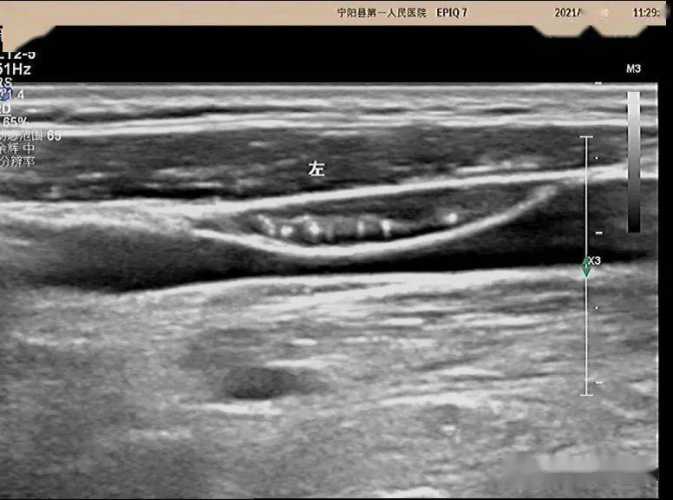

甲状腺B超对备孕没影响。B超是超声波检查,不像X光有辐射。我怀老大前也做过甲状腺B超,当时也担心,后来医生说没事。做B超就是探头在脖子上滑滑,很快就好。备孕检查甲状腺很重要,能看有没有结节、功能正不正常。我朋友备孕时查出甲状腺问题,调好了再怀,现在宝宝很健康。做B超就放宽心去,别自己吓自己,检查好了心里也踏实。